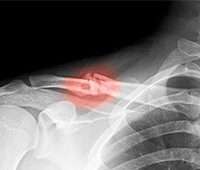

6.How does one have a dislocated joint?

Dislocations are usually caused due to a trauma or as a sports injury. Falls associated with contact sports such as football, basketball etc can lead to a dislocation.

Additionally, a fall on the outstretched hand and trauma due to a motor accident, too can cause dislocation.